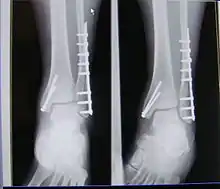

| X-ray of trimalleolar fracture repair before and after ORIF surgery | |

Surgical repair using open reduction and internal fixation is generally required, and because there is no lateral restraint of the foot, the ankle cannot bear any weight while the bone knits. This typically takes six weeks in an otherwise healthy person, but can take as much as twelve weeks. Non-surgical treatment may sometimes be considered in cases where the patient has significant health problems or where the risk of surgery may be too great.[1]